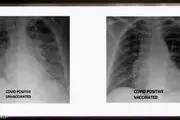

• تفاوت ریه‌های فرد واکسینه شده و فرد واکسینه نشده/ببینید

تفاوت ریه‌های فرد واکسینه شده و فرد واکسینه نشده/ببینید

یک پزشک آمریکایی تصویری را از ریه های فرد واکسینه شده و فرد واکسینه نشده مبتلا به کرونا منتشر کرد.

۲۳ مرداد ۱۴۰۰